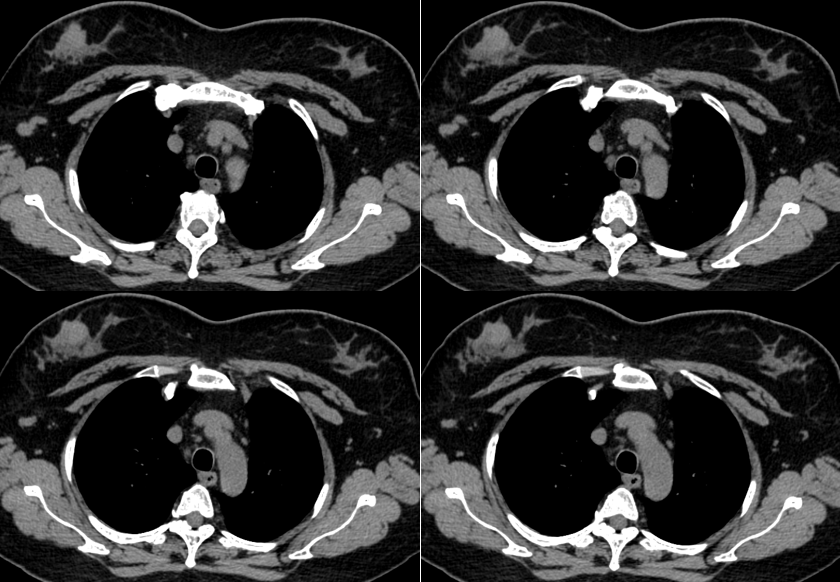

MG/CT:

乳腺炎:包括急、慢性乳腺炎和乳腺脓肿,多见于产后哺乳期妇女,急性乳腺炎常有典型的临床症状-红、肿、热、痛;若治疗不及时可形成慢性乳腺炎或乳腺脓肿。MG 表现片状致密影,边缘模糊,患处皮肤水肿增厚,皮下脂肪层模糊;MRI-T1WI 表现为片状低信号,T2WI 高信号,信号强度不均匀,边缘模糊,皮肤水肿、增厚,增强 MRI 通常表现为轻至中度强化,且以延迟强化为主。